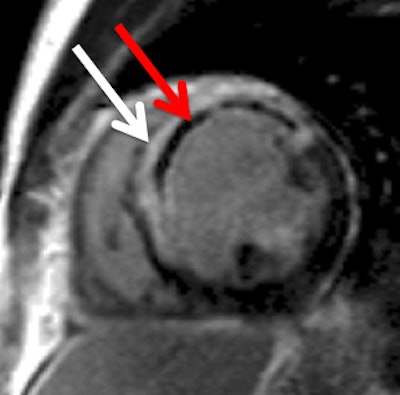

Late gadolinium enhancement image shows a large anteroseptal myocardial infarction (white arrow) with a central core of microvascular obstruction (red arrow). Images courtesy of Dr. Mark Westwood.

Late gadolinium enhancement image shows a large anteroseptal myocardial infarction (white arrow) with a central core of microvascular obstruction (red arrow). Images courtesy of Dr. Mark Westwood."Cardiac MRI provides reliable anatomical and functional assessment of the heart and evaluation of myocardial viability and coronary artery disease," he explained. "It is especially useful for diagnosing myocardial infarction. Cardiac MR late gadolinium enhancement can quantify the size, location, and transmural extent of the infarct."